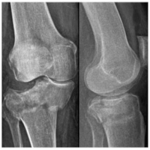

530

Fracturas de platillo tibial tipo II-III de Schatzker tratadas con aloinjerto óseo impactado o técnica de rafting. ¿Es necesario llenar el vacío? Estudio de cohortes comparativo en 80 pacientes

Sebastián Pereira, Germán Garabano, Andrés Juri, Leonel Pérez Alamino, Joaquín Rodríguez, César Á. Pesciallo, Fernando Bidolegui

556

Evaluación de la clasificación de las fracturas de platillo tibial según Schatzker-Kfuri utilizando radiografías y tomografía. Comparación entre el observador experto y el modelo ChatGPT-4o

Héctor A. Rivadeneira Jurado, Elias A. Rivadeneira Jurado, Daniel Espinoza Freire, Andrés F. Samaniego, Ezequiel Lulkin, Fernando Bidolegui, Sebastián Pereira